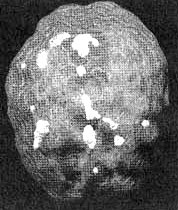

Мозг Роба. Результаты сканирования SPECT

Трехмерное изображение — активный мозг, вид сбоку.

До лечения: обратите внимание на выраженное усиление активности в поясной системе (см. стрелку).

После лечение Anafranil. Активность поясной системы нормализовалась.

После трех лет неуклонного улучшения состояния на фоне приема Anafranil (оба раза, когда предпринимались попытки снизить дозу, симптомы возвращались), повторное сканирование показало нормализацию функции мозга.